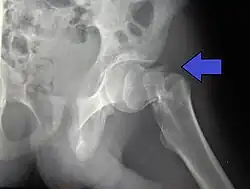

X-rays of the affected hip usually make the diagnosis obvious; AP (anteroposterior) and lateral views should be obtained.

For low-grade fractures (Garden types 1 and 2), standard treatment is fixation of the fracture in situ with screws or a sliding screw/plate device. This treatment can also be offered for displaced fractures after the fracture has been reduced.

In elderly patients with displaced or intracapsular fractures surgeons may decide to perform a hemiarthroplasty, replacing the broken part of the bone with a metal implant.[39] However, in elderly people who are medically well and still active, a total hip replacement may be indicated. Independently mobile older adults with hip fractures may benefit from a total hip replacement instead of hemiarthroplasty.[40]